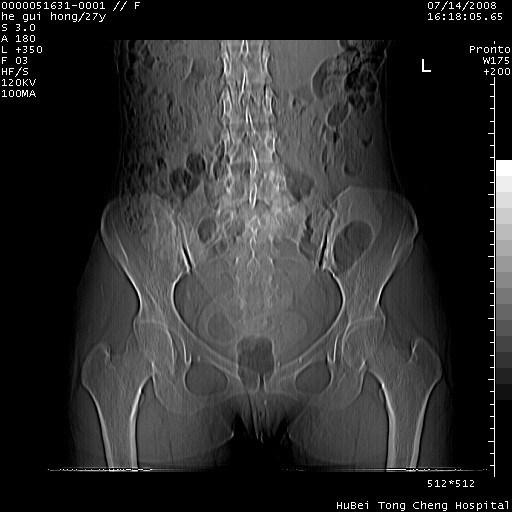

以下是引用杀毒软件在2008-7-20 8:03:00的发言:[br]支持双侧卵巢囊腺瘤可能性大!

以下是引用zjzjr在2008-7-20 13:36:00的发言:[br]双侧附件囊腺瘤可能性大!